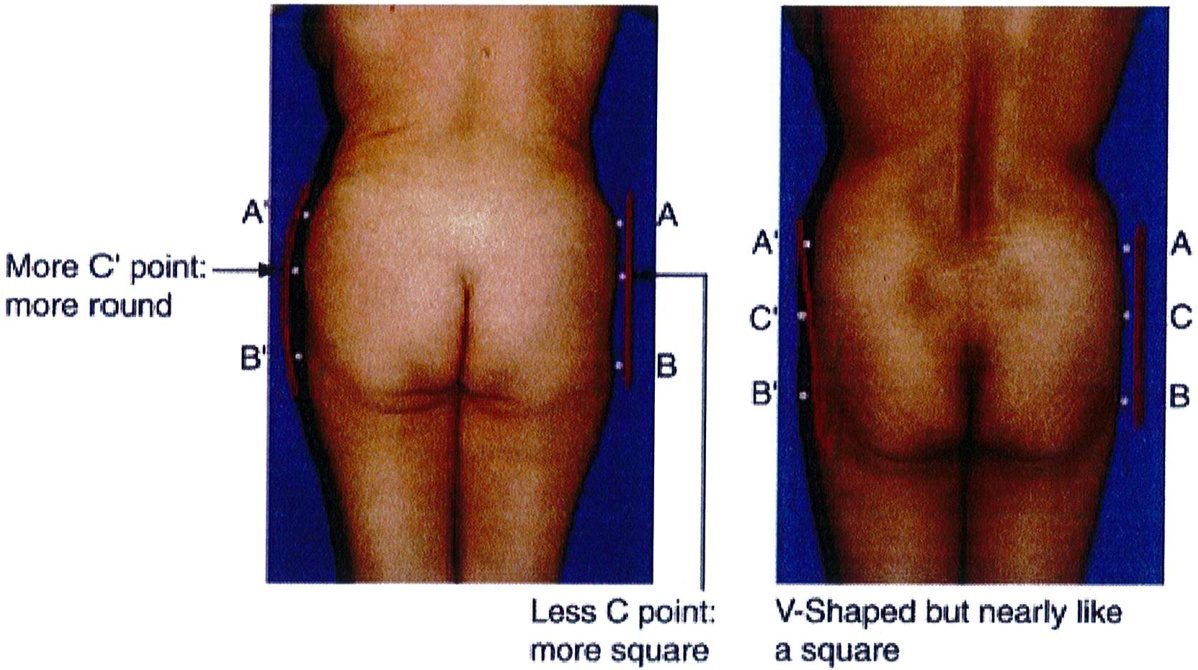

Việc phân loại các loại khung được thực hiện bằng cách so sánh và đối chiếu lượng chất béo có sẵn trong 3 vùng cụ thể. Điểm nhô ra nhất ở vùng hông, giới hạn trên được đánh dấu là điểm A, điểm nhô ra nhiều nhất ở vùng đùi ngoài

là điểm B và điểm giữa mặt ngoài mông là điểm C (Hình 4).

Sự kết nối các điểm A và B ở mỗi bên của cơ thế dẫn tới việc xác định 4 loại khung cơ bản: Hình chữ A, hình chữ V, hình vuông và hình tròn (Hình 5).

Điểm C có 2 chức năng: Đầu tiên là giúp phân biệt dạng mông tròn hay vuông. Mông tròn có lượng mỡ dư thừa ở điểm C này nhưng mông vuông thì có lượng mỡ bằng nhau hoặc lệch bên (Hình 5). Chức năng thứ hai và cũng là quan trọng nhất của điểm C là chúng giúp đánh giá mức độ lõm xuống ở điểm C trong mông vuông, mông hình chữ A hoặc hình chữ V. Mức độ lõm này được phân thành nhiều mức độ: 0, nhẹ, vừa, nặng (Hình 6).

Dạng tròn gặp ở khoảng 15% số bệnh nhân. Dạng này có đặc điểm là xuất hiện lượng mỡ thừa ở điểm C. Khi cả 3 điểm (A, B và C) được kết nối với nhau, một đường cong hình chữ C sẽ được hình thành (Hình 10). Điểm C rất quan trọng vì nó giúp phân biệt khung tròn với khung vuông. Khi điểm C lõm dần, khung từ dạng tròn chuyển dạng vuông.